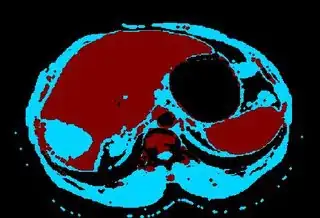

I extracted liver for this sample image and the output is like this Output image for sample image. My implementation code is